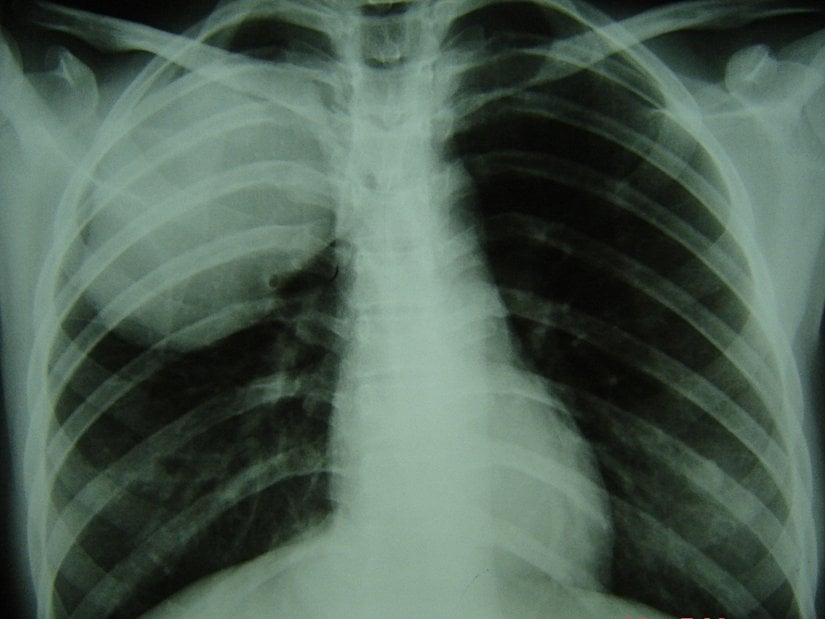

Kistik ekinokokkoz tanısı görüntüleme teknikleri, ağırlıklı olarak ultrasonografi (USG), bilgisayarlı tomografi, X-ışını incelemeleri ve serolojik testlerle spesifik serum antikorlarının tespiti yoluyla kist yapılarının tanımlanmasına dayanır. Serolojik yöntemler genelde ikinci planda ve tanıyı doğrulamada ve tedavi sonrası hastaların izlenmesinde yararlıdır. Bu amaçla ELISA ve indirekt hemaglütinasyon (IHA) gibi serolojik yöntemler kullanılmaktadır ancak bu yöntemlerin özgüllüğü tatmin edici bulunmamaktadır. Karaciğer yerleşimli kistlerin %10 ila 20'sinin, akciğer yerleşimli kistlerin ise yaklaşık %40'ının saptanabilir spesifik serum antikorları (IgG) üretmediği ve bu nedenle yanlış negatif sonuçlar verdiği tespit edilmiştir.[1] Beyin, kemik, ve göz yerleşimli kistler genellikle hiç antikor yanıtına neden olmaz.[1]Bu nedenlerle teşhiste görüntüleme teknikleri öne çıkmaktadır.

Radyolojik yöntemler enfeksiyonun bireysel ve kitlesel tanısında öne çıkmaktadır. Görüntüleme yöntemleri arasından ultarosongrafi (USG) kolay uygulanabilirliği, hızlı, ucuz ve zararsız olması bakımından önemlidir. Bu yöntem kistlerin yeri, büyüklüğü, sayısı gibi çok önemli bilgileri vermektedir.